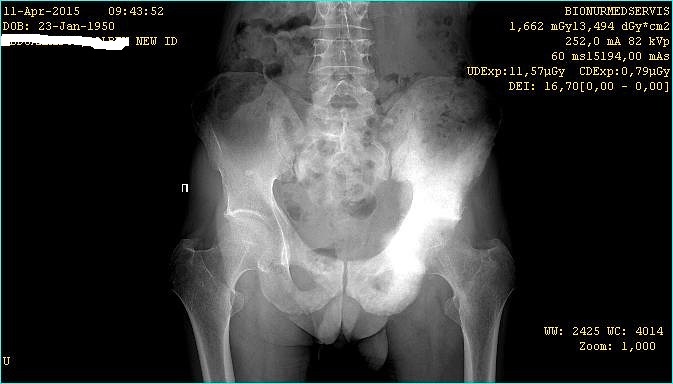

Снимок т/б сустава

Здравствуйте уважаемые коллеги. Хочу просить помощи в анализе представленного снимка. Пациент прислал по сети и попросили прокомментировать. У меня возникли затруднения с дифференцировкой данного новообразования и поэтому прошу помощи коллег, возможно, кто-то встречал в своей практике подобные случаи.

Возможно болезнь Педжета

Саркома таза?

Со слов родственников брали биопсию но точного ответа не получили. В анамнезе 2005 субтотальая резекция желудка. Я рекомендовал сцинтиграфию. Если родственники прислушаются то возможно отпишутся о результате...

На сцинтиграфии накопление характерно для метастазов.